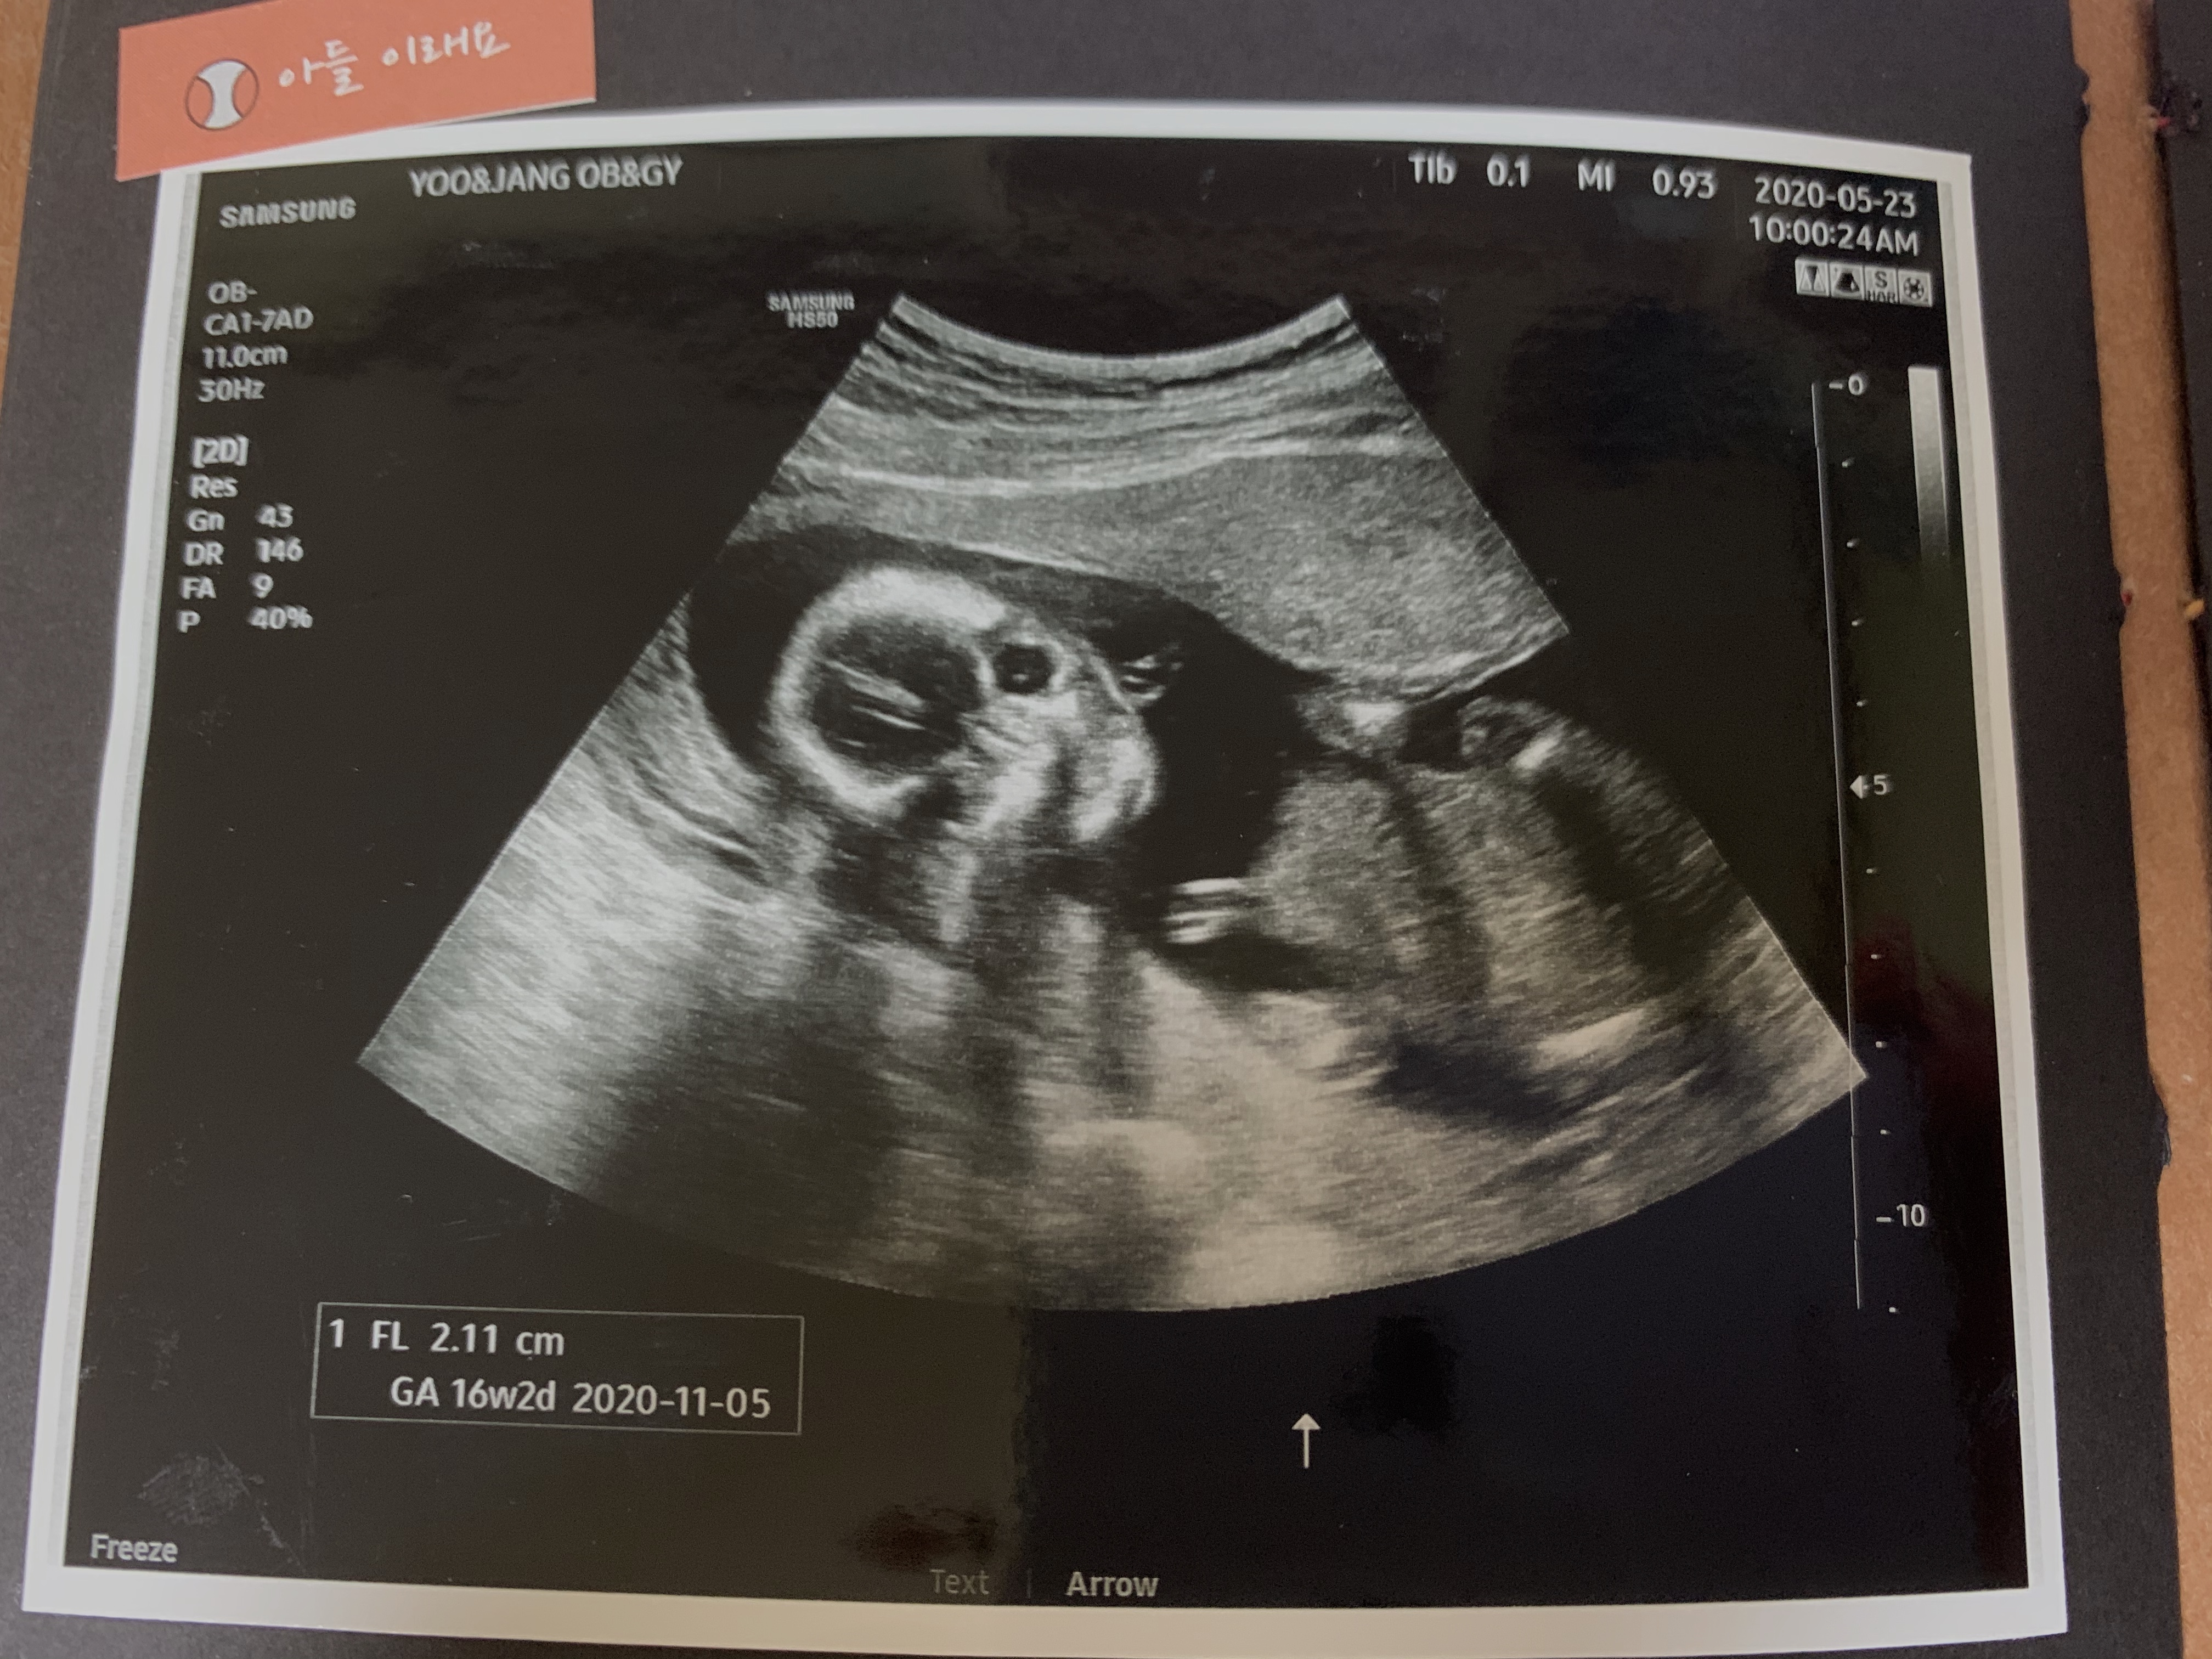

1.1차 정밀초음파&통합선별검사 임신 12주차는 중요한 시기로 아이가 많이 커져 배 초음파가 가능해져 1차 정밀초음파검사와 통합선별검사를 하게 됩니다.

정밀초음파는 1차(10~13주), 2차(20~21주)에 시행되는데, 1차 정밀초음파 검사: 태아목 투명대(NT) 두께 측정으로 태아의 염색체, 심장에 이상이 있는지 확인합니다.보통 2.5mm 미만이 정상입니다(목투명대란 아기를 둘러싼 차양막에서 목까지의 빈 부분입니다.)

2차 정밀 초음파 검사 : 태아의 성장(외형, 내부 장기 등)을 파악합니다.분만일 기준 만 35세 이상 산모, 이전에 염색체 이상이 있는 아이를 임신했던 산모 등 위험군이 아니라면 보통 통합선별검사, 1차 2차 산모의 혈액검사를 통해 다운증후군 등 이상 유무를 파악합니다.하지만 직접 태아의 염색체를 확인하는 방법이 아니기 때문에 진단률은 90~94%로 진단을 놓칠 가능성이 5~10%가 됩니다.